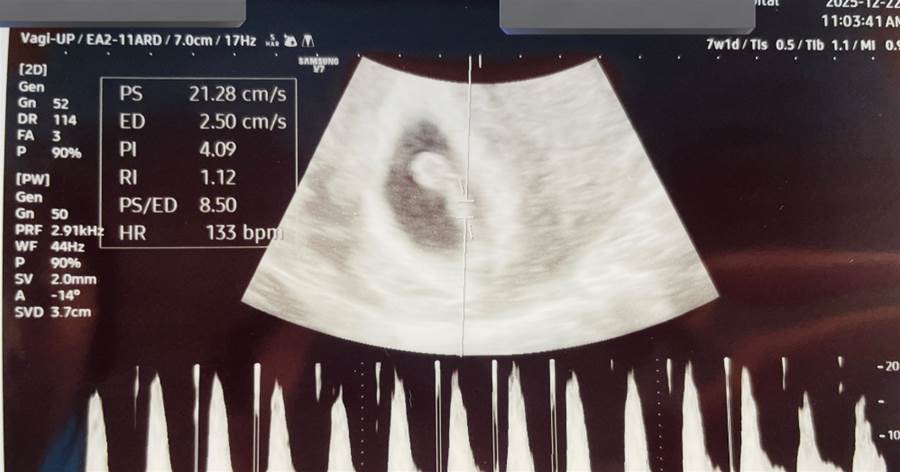

一緒に産婦人科にも行きました。

エコーを見ながら、先生に「元気ですよ」と言われて、

赤ちゃんの心臓の音を聞いたとき、彼も隣で笑っていたんです。

あのときの空気、今でも忘れられません。

「すごいね」って、小さく呟いた彼の声。

この子の心臓の音を、私はもう聞いてしまった。

あの音を知ってしまった以上、

“なかったこと”にはできません。